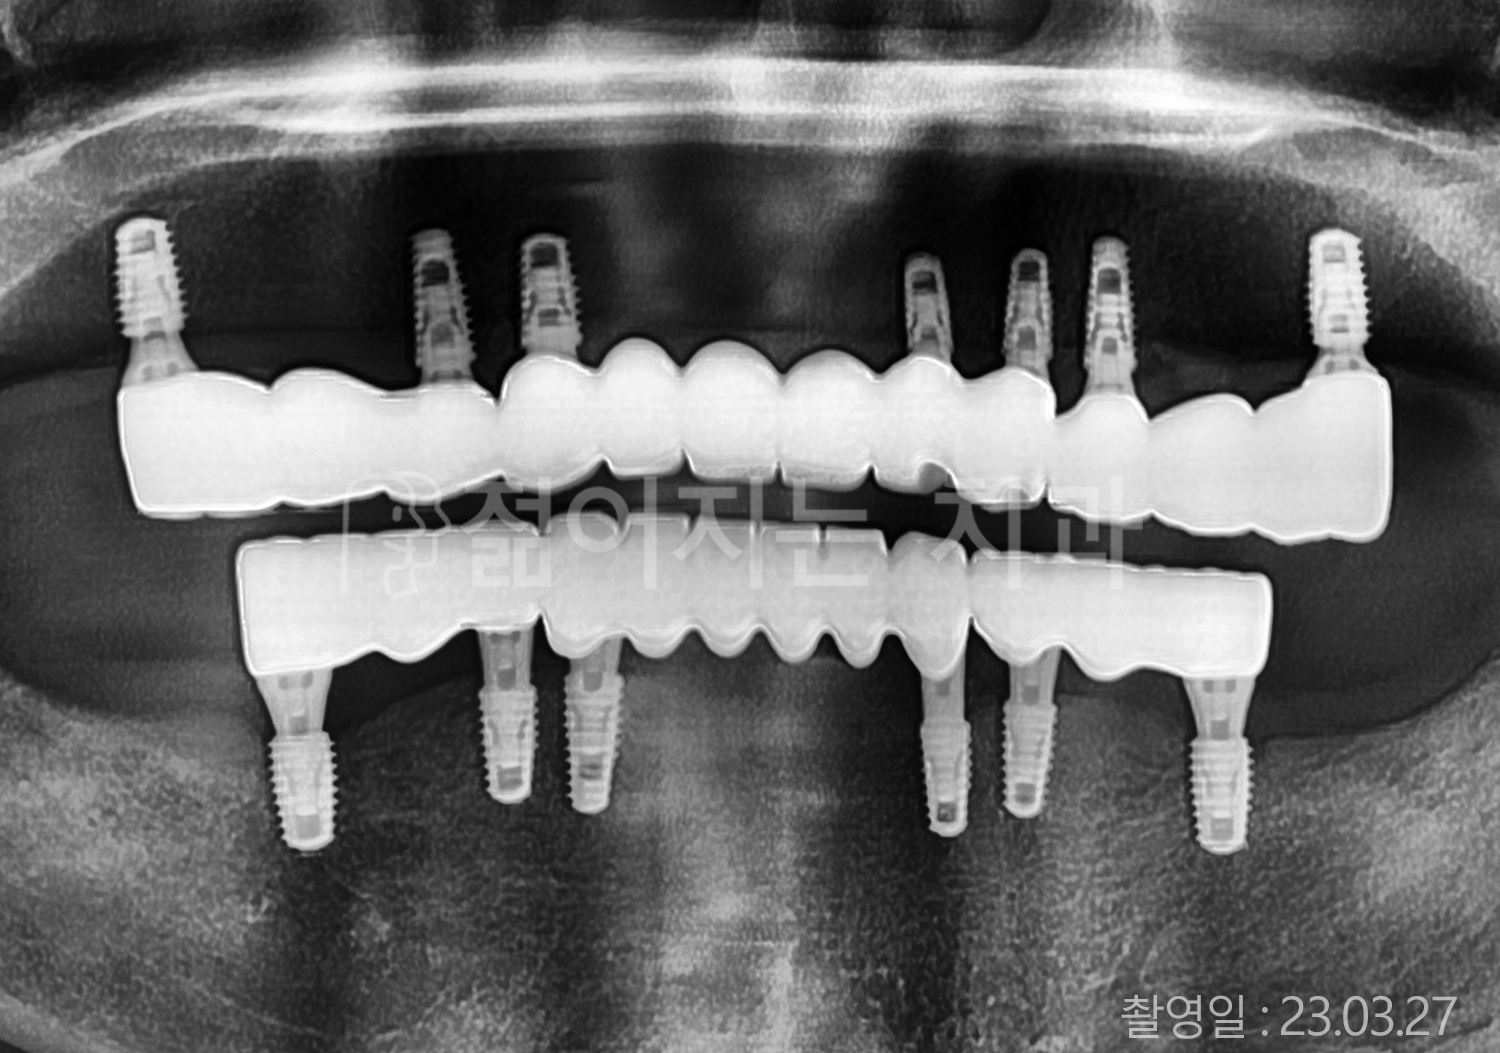

• 70대 고혈압, 당뇨 전체치아 10개 이상 임플란트

• 50대 고혈압, 당뇨 전체치아 10개 이상 임플란트

• 60대 고혈압, 당뇨 전체치아 10개 이상 임플란트

• 50대 전체치아 10개 이상 임플란트

• 70대 당뇨 전체치아 10개 이상 임플란트

• 80대 전체치아 10개 이상 임플란트

• 40대 전체치아 10개 이상 임플란트

• 60대 고협압, 고지혈증 전체치아 10개 이상 임플란트

• 60대 전체치아 10개 이상 임플란트